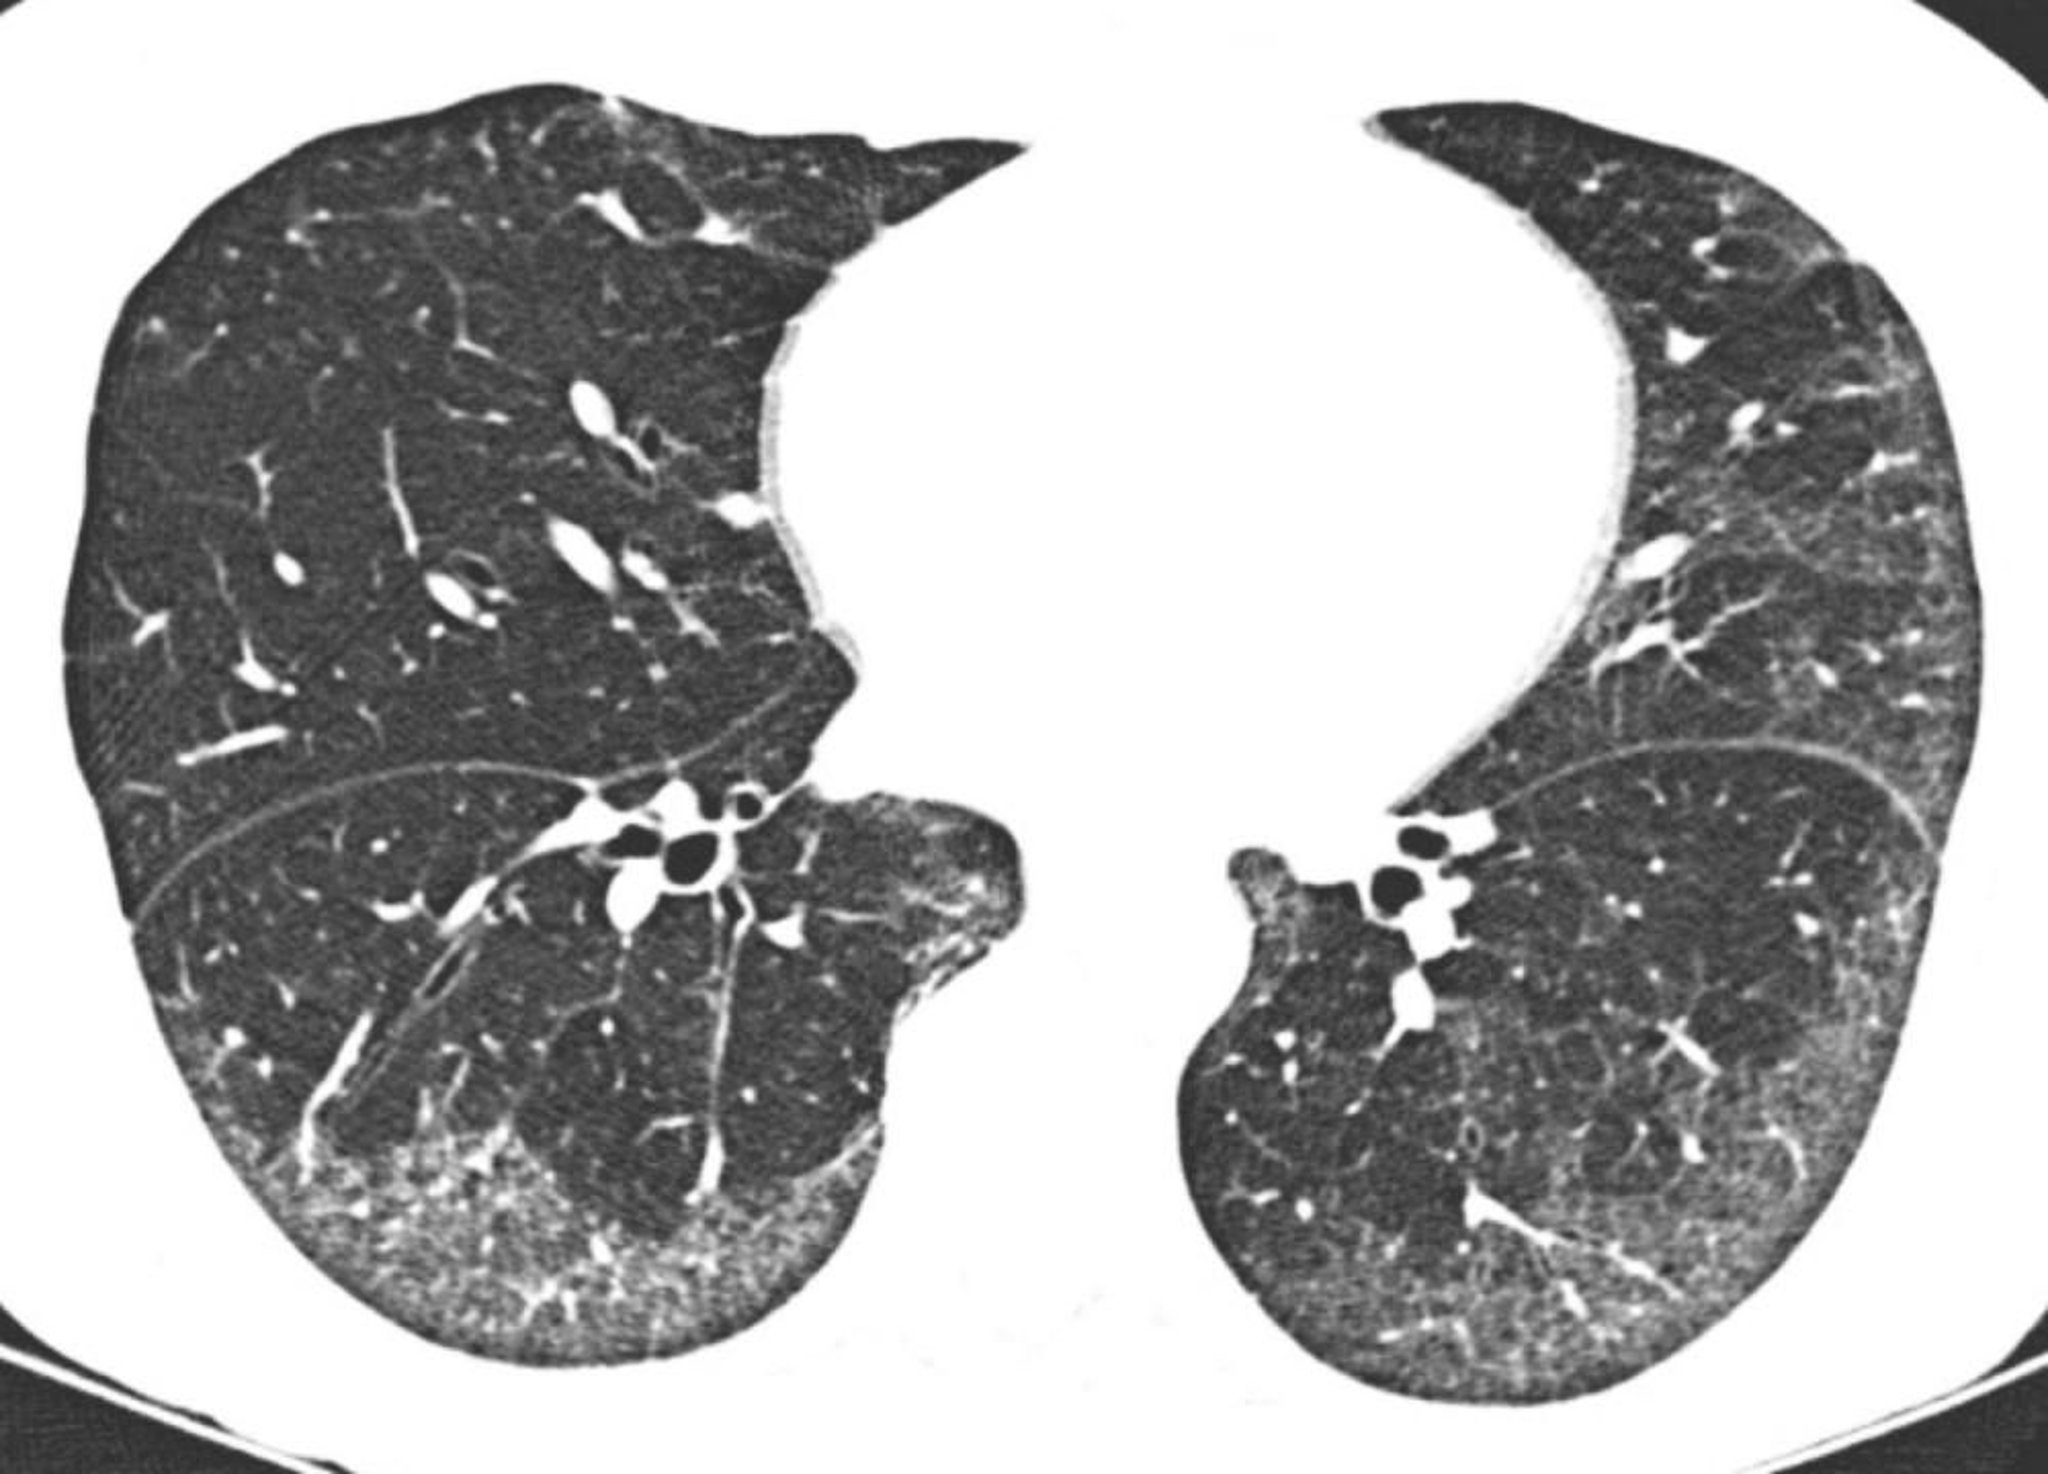

Neumonía intersticial idiopática inespecífica

La TC de alta resolución muestra opacidades en vidrio esmerilado predominantemente subpleurales y basales. La preservación relativa de los pulmones directamente debajo de las superficies pleurales es típica de la neumonía intersticial no específica.

Image courtesy of Harold R. Collard, MD.